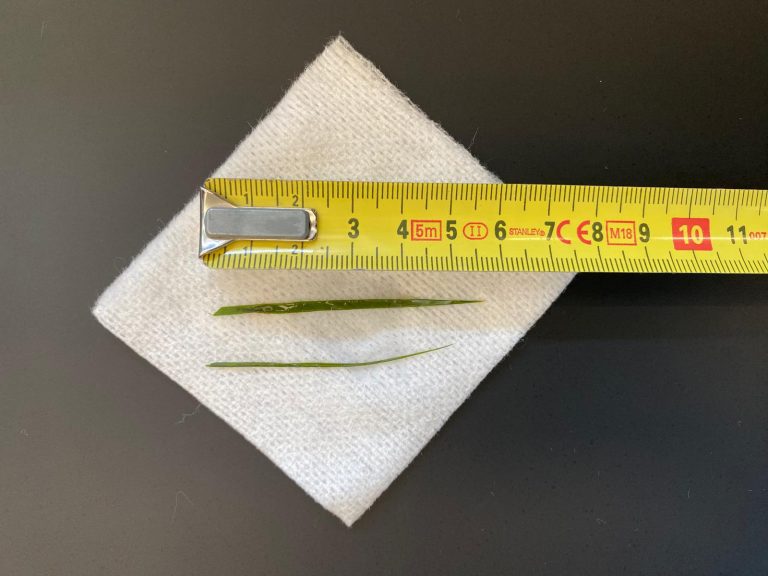

In de loop van de volgende dag werd de hoeveelheid lucht, die we konden afzuigen, steeds minder en ging het steeds beter met Jessie. Omdat het voor Jessie prettiger was, ging Jessie het einde van de dag naar huis. Jessie was enorm blij om haar baasje te zien en was eigenlijk wat te wild in de begroeting. Na 1,5 uur belde de eigenaar ons op, dat het niet goed ging, dus Jessie moest gelijk terugkomen. Jessie was weer erg kortademig. Dit was verbazend, gezien hoe goed het eigenlijk ging. We hebben nieuwe röntgenfoto’s gemaakt en zagen weer veel lucht. Mogelijk was er toch weer iets gaan lekken door de eerdere activiteit.